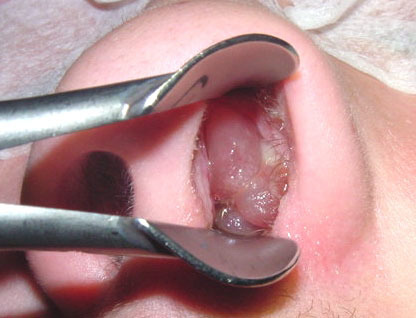

Qx y pólipos: objetivo, tipo de cirugía y patología en la que es primera opción

Abolir la obstrucción nasal

CENS: cirugía endoscópica nasosinusal

Primera opción en pólipo de Killian o antrocoanal

pólipo de Killian o antrocoanal características morfológicas (dónde y cómo se presenta y extensión)